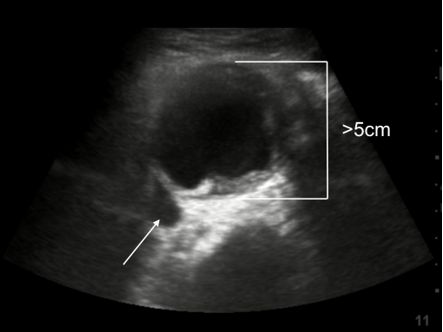

RUSH 主动脉扩张或皮瓣?图像

主动脉瘤直径:5 cm